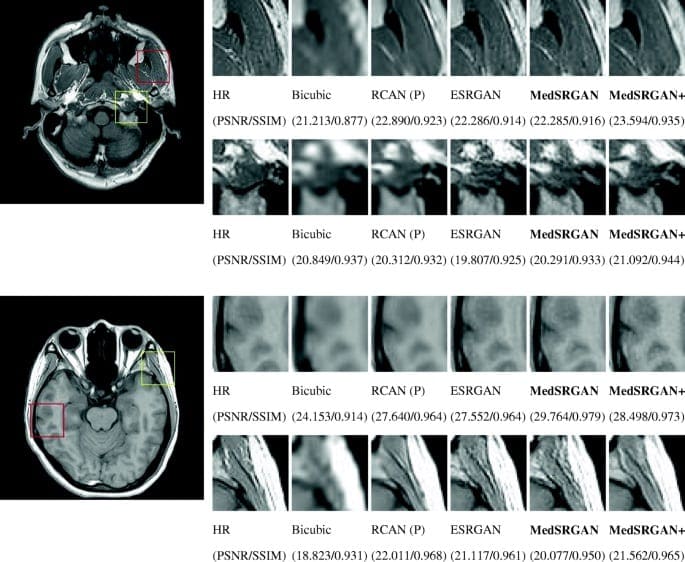

- Image super-resolution — upscaling low-res images to high-res without noticeable upscaling artefacts.

Figure 5. Upscaling image using GAN (SRGAN) in comparison with non-machine learning bicubic interpolation method and non-GAN ML method SRResNet (source)

The possibility of image improvement allows us to implement GANs in medicine for Photo-Realistic Single Image Super-Resolution. Why is this significant?

The reason for the high demand for GANs in healthcare is that images should fit particular requirements and be high-quality. High image quality can be difficult to obtain under certain measurement protocols, for example, there is a strong need to decrease the effect of radiation on patients when using low-dose scanning in Computer Tomography (CT, to reduce the harmful effect on people with certain health pre-conditions such as lung cancer) or MRI. It has the effect of complicating efforts to obtain good quality pictures because of the poor quality scans.

Super-resolution improves the captured images and can remove the noise quite well, however adoption of GANs in the medical area is quite slow as many experiments and trials have to be made due to safety concerns. When dealing with healthcare, it is mandatory to involve a number of domain experts to evaluate the models and ensure the denoising does not distort the actual content of the image in some way that could lead to an incorrect diagnosis.